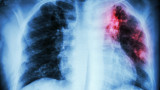

Започват безплатни прегледи за туберкулоза в цялата страна.

Отчита се тенденция за трайно намаляване на заболяемостта от туберкулоза - от 23.8 на 100 000 население през 2013 г. до 13.5 на 100 000 през 2023 г.

Туберкулозата е лечима и предотвратима, стига да бъде открита навреме и да бъде проведено качествено лечение, посочват от здравното министерство.